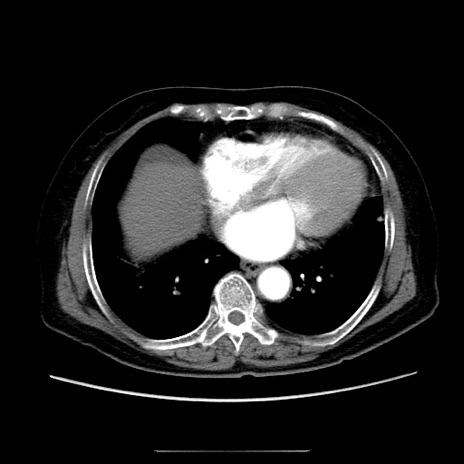

冠状断像

【症例】70歳代女性

【主訴】お腹が張る

【現病歴】1週間くらい前から腹部膨満の自覚あり。昨日夜から増悪したため、本日救急外来受診。

【身体所見】意識清明、BT 36.5℃、BP 165/106mmHg、HR 80bpm、SpO2 98%、腹部:膨満、軟、自発痛・圧痛なし、触診にて不快感あり、腸蠕動音:減弱

【データ】WBC 12600、CRP 1.04